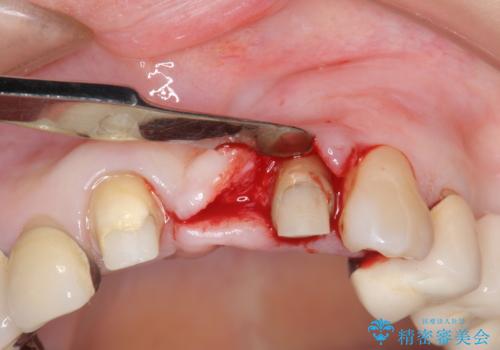

挺出について

虫歯が深くなった場合、挺出や歯周外科を行い歯周組織の状態を改善することでより安定した状態で予知性の高いセラミックブリッジを製作することが可能となります。